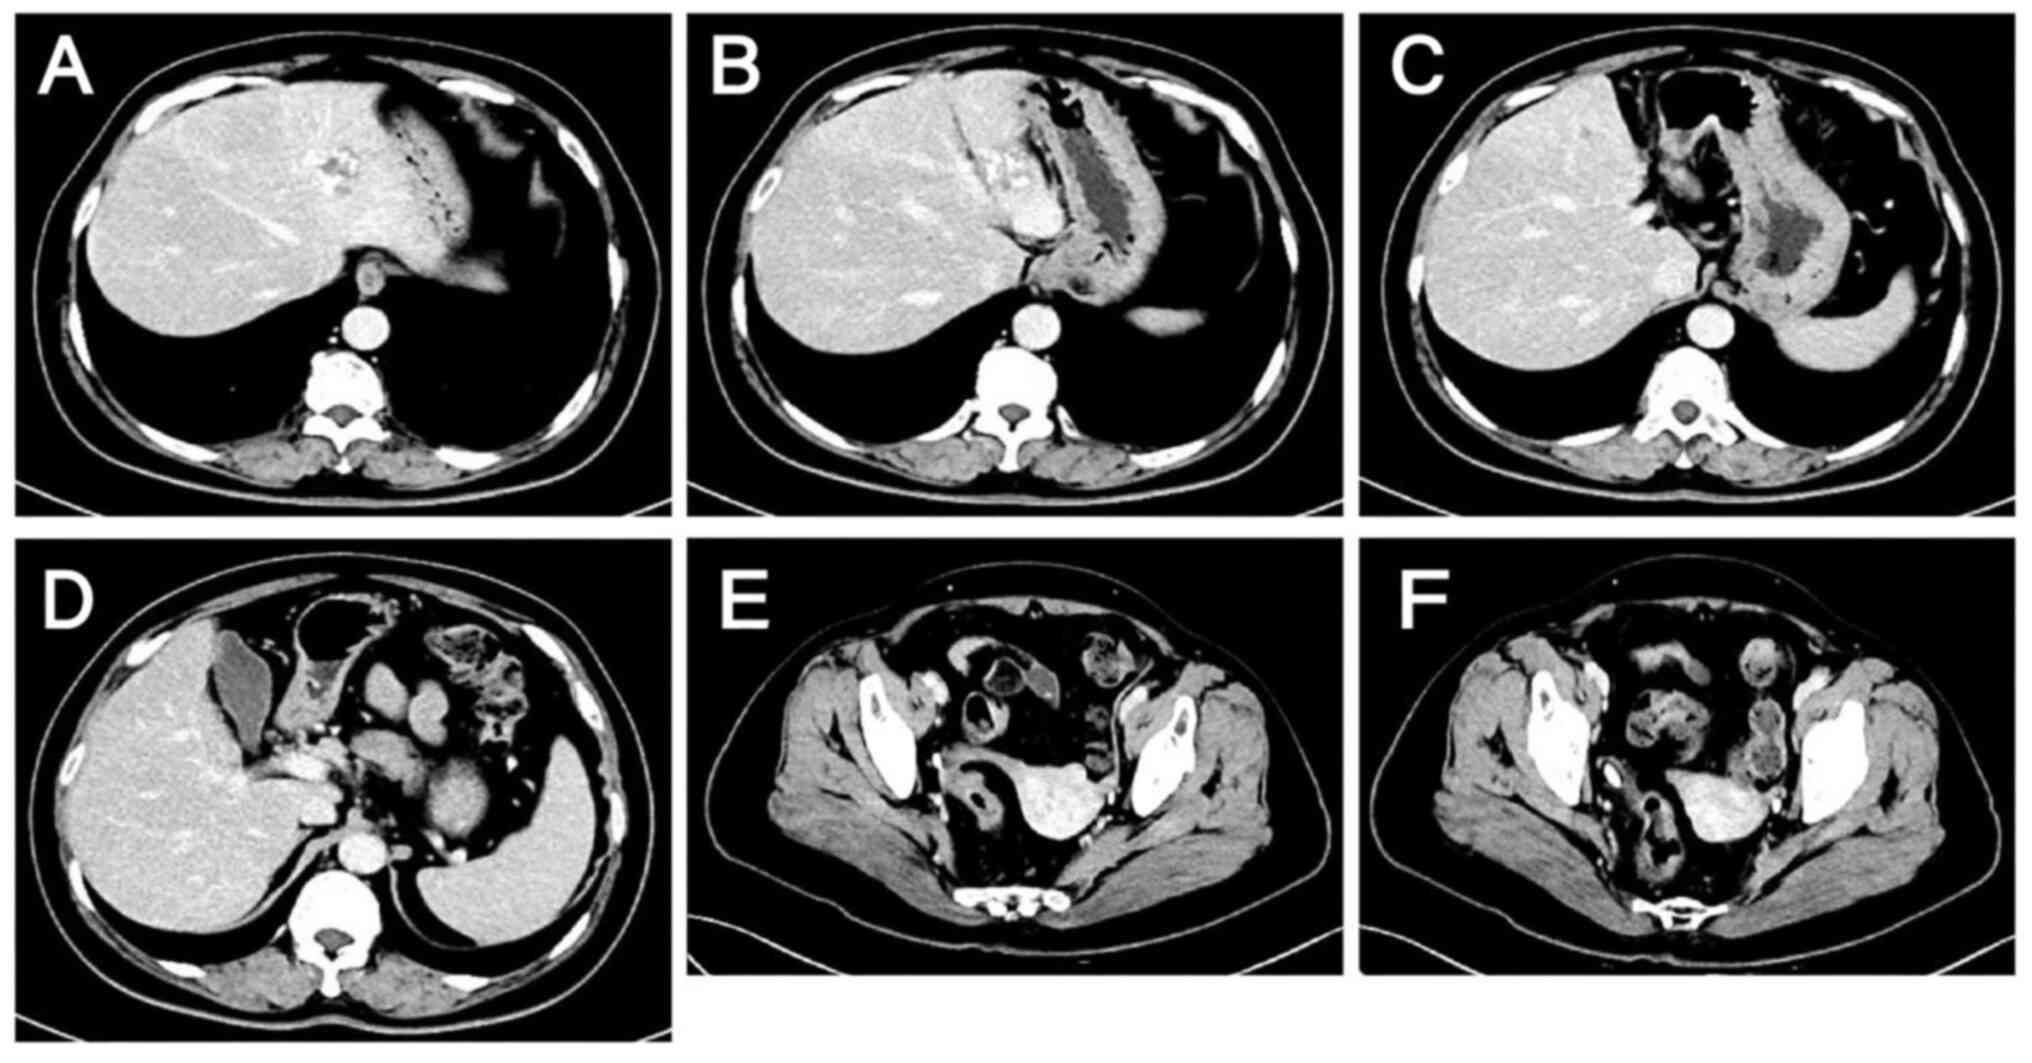

A 60-year-old woman with complaints of abdominal pain and passage of bloody stools was admitted to Hebei General Hospital (Shijiazhuang, China) in October 2023. Contrast-enhanced scans of the abdomen and pelvis revealed wall thickening in the sigmoid colon and rectum, enlarged lymph nodes in the surrounding area suggestive of malignancy, and low-density shadows in the S2, S3 and S4 segments of the liver that were thought to be metastases (Fig. 1). Colonoscopy suggested rectal cancer, and a tissue biopsy revealed moderately and well-differentiated adenocarcinoma with necrosis (Fig. 2). Magnetic resonance images revealed liver metastases in the S2, S3 and S4 segments and two enlarged lymph nodes, one anterior and one posterior to the portal vein (Fig. 3). Digestive tract tumor marker levels, including carcinoembryonic antigen, carbohydrate antigen (CA)242 and CA724, were all higher than normal (Fig. 4). NGS of a biopsy specimen obtained by colonoscopy suggested that KRAS, NRAS and BRAF were WT (Figs. S1 and S2). It also revealed that ERBB2 (HER2) had a mutation abundance 8.3-fold higher than the reference level, suggesting possible resistance to panitumumab and cetuximab. In addition, TP53 exon5c.399del had a mutation abundance of 31.61%, suggesting microsatellite stability. The NGS was performed by Novogene Bioinformatics Technology Co., Ltd. DNA extraction and library preparation was performed using the Qiagen QIAamp DNA FFPE Kit (Qiagen, GmbH) and Agilent SureSelect XT HS2 (Agilent Technologies, Inc.), respectively. Sample quality was assessed by pathological analysis of tumor cell content, nucleic acid quality assessment (total DNA amount, DNA degradation degree and total pre-library amount) and sequencing quality assessment (average sequencing depth, coverage uniformity, genome alignment rate and base quality Q30 proportion). The hybridization capture method was used, and the read length and sequencing direction were double ends of 150 bp and double-end sequencing, respectively. The sequencing platform and sequencing kit were the Illumina NextSeq 550 and Illumina NextSeq 550 High Output kits (Illumina, Inc.), respectively. Final library loading concentration was 1.2–1.8 pM. The software used for the analysis included CNVkit (version 0.9.9; University of California), GATK Mutect2 (version 4.1.8.1; Broad Institute of MIT and Havard) and PierianDx (version 7.3; Velsera, Inc.).

Initial assessment of the lesions by

computed tomography on October 15, 2023. (A-D) Metastatic liver

lesions: Slightly hypodense shadows are visible in the S2, S3 and

S4 segments of the liver, suggestive of metastasis. (E and F) Colon

lesions: Thickening of the sigmoid-rectal wall and enlargement of

the peripheral lymph nodes are indicative of malignancy. Lesions

are indicated by arrows.

Figure 1.

Initial assessment of the lesions by computed tomography on October 15, 2023. (A-D) Metastatic liver lesions: Slightly hypodense shadows are visible in the S2, S3 and S4 segments of the liver, suggestive of metastasis. (E and F) Colon lesions: Thickening of the sigmoid-rectal wall and enlargement of the peripheral lymph nodes are indicative of malignancy. Lesions are indicated by arrows.

Following discussions among the multidisciplinary team and considering the patient's preference for surgery, neoadjuvant therapy was initiated, with plans to proceed to surgery for the primary CRC lesions and liver metastases if the treatment was effective. After obtaining informed consent, the patient was treated with two cycles of a modified FOLFOX6 regimen based on a body surface area of 1.66 m2, comprising oxaliplatin 140 mg + leucovorin calcium 600 mg + fluorouracil 0.625 g by intravenous injection + fluorouracil 3.75 g. This regimen was administered by continuous intravenous drip on 13 days post admission and 28 days post admission. However, after the two cycles, no reduction in the size of the tumor lesions was evident (Fig. 5) and the tumor marker levels remained elevated (Fig. 4), suggesting poor treatment efficacy.

Lesions after 1 cycle of chemotherapy

as evaluated by computed tomography on November 10, 2023. (A-D)

Metastatic liver lesions: No marked change is visible compared with

those on October 15, 2023. (E and F) Colon lesions: Thickening of

the sigmoid-rectal wall is slightly less severe than that on

October 15, 2023, but no changes are evident in the surrounding

enlarged lymph nodes.

Figure 5.

Lesions after 1 cycle of chemotherapy as evaluated by computed tomography on November 10, 2023. (A-D) Metastatic liver lesions: No marked change is visible compared with those on October 15, 2023. (E and F) Colon lesions: Thickening of the sigmoid-rectal wall is slightly less severe than that on October 15, 2023, but no changes are evident in the surrounding enlarged lymph nodes.